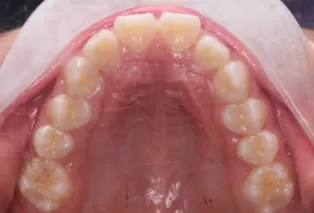

Intraoral photos